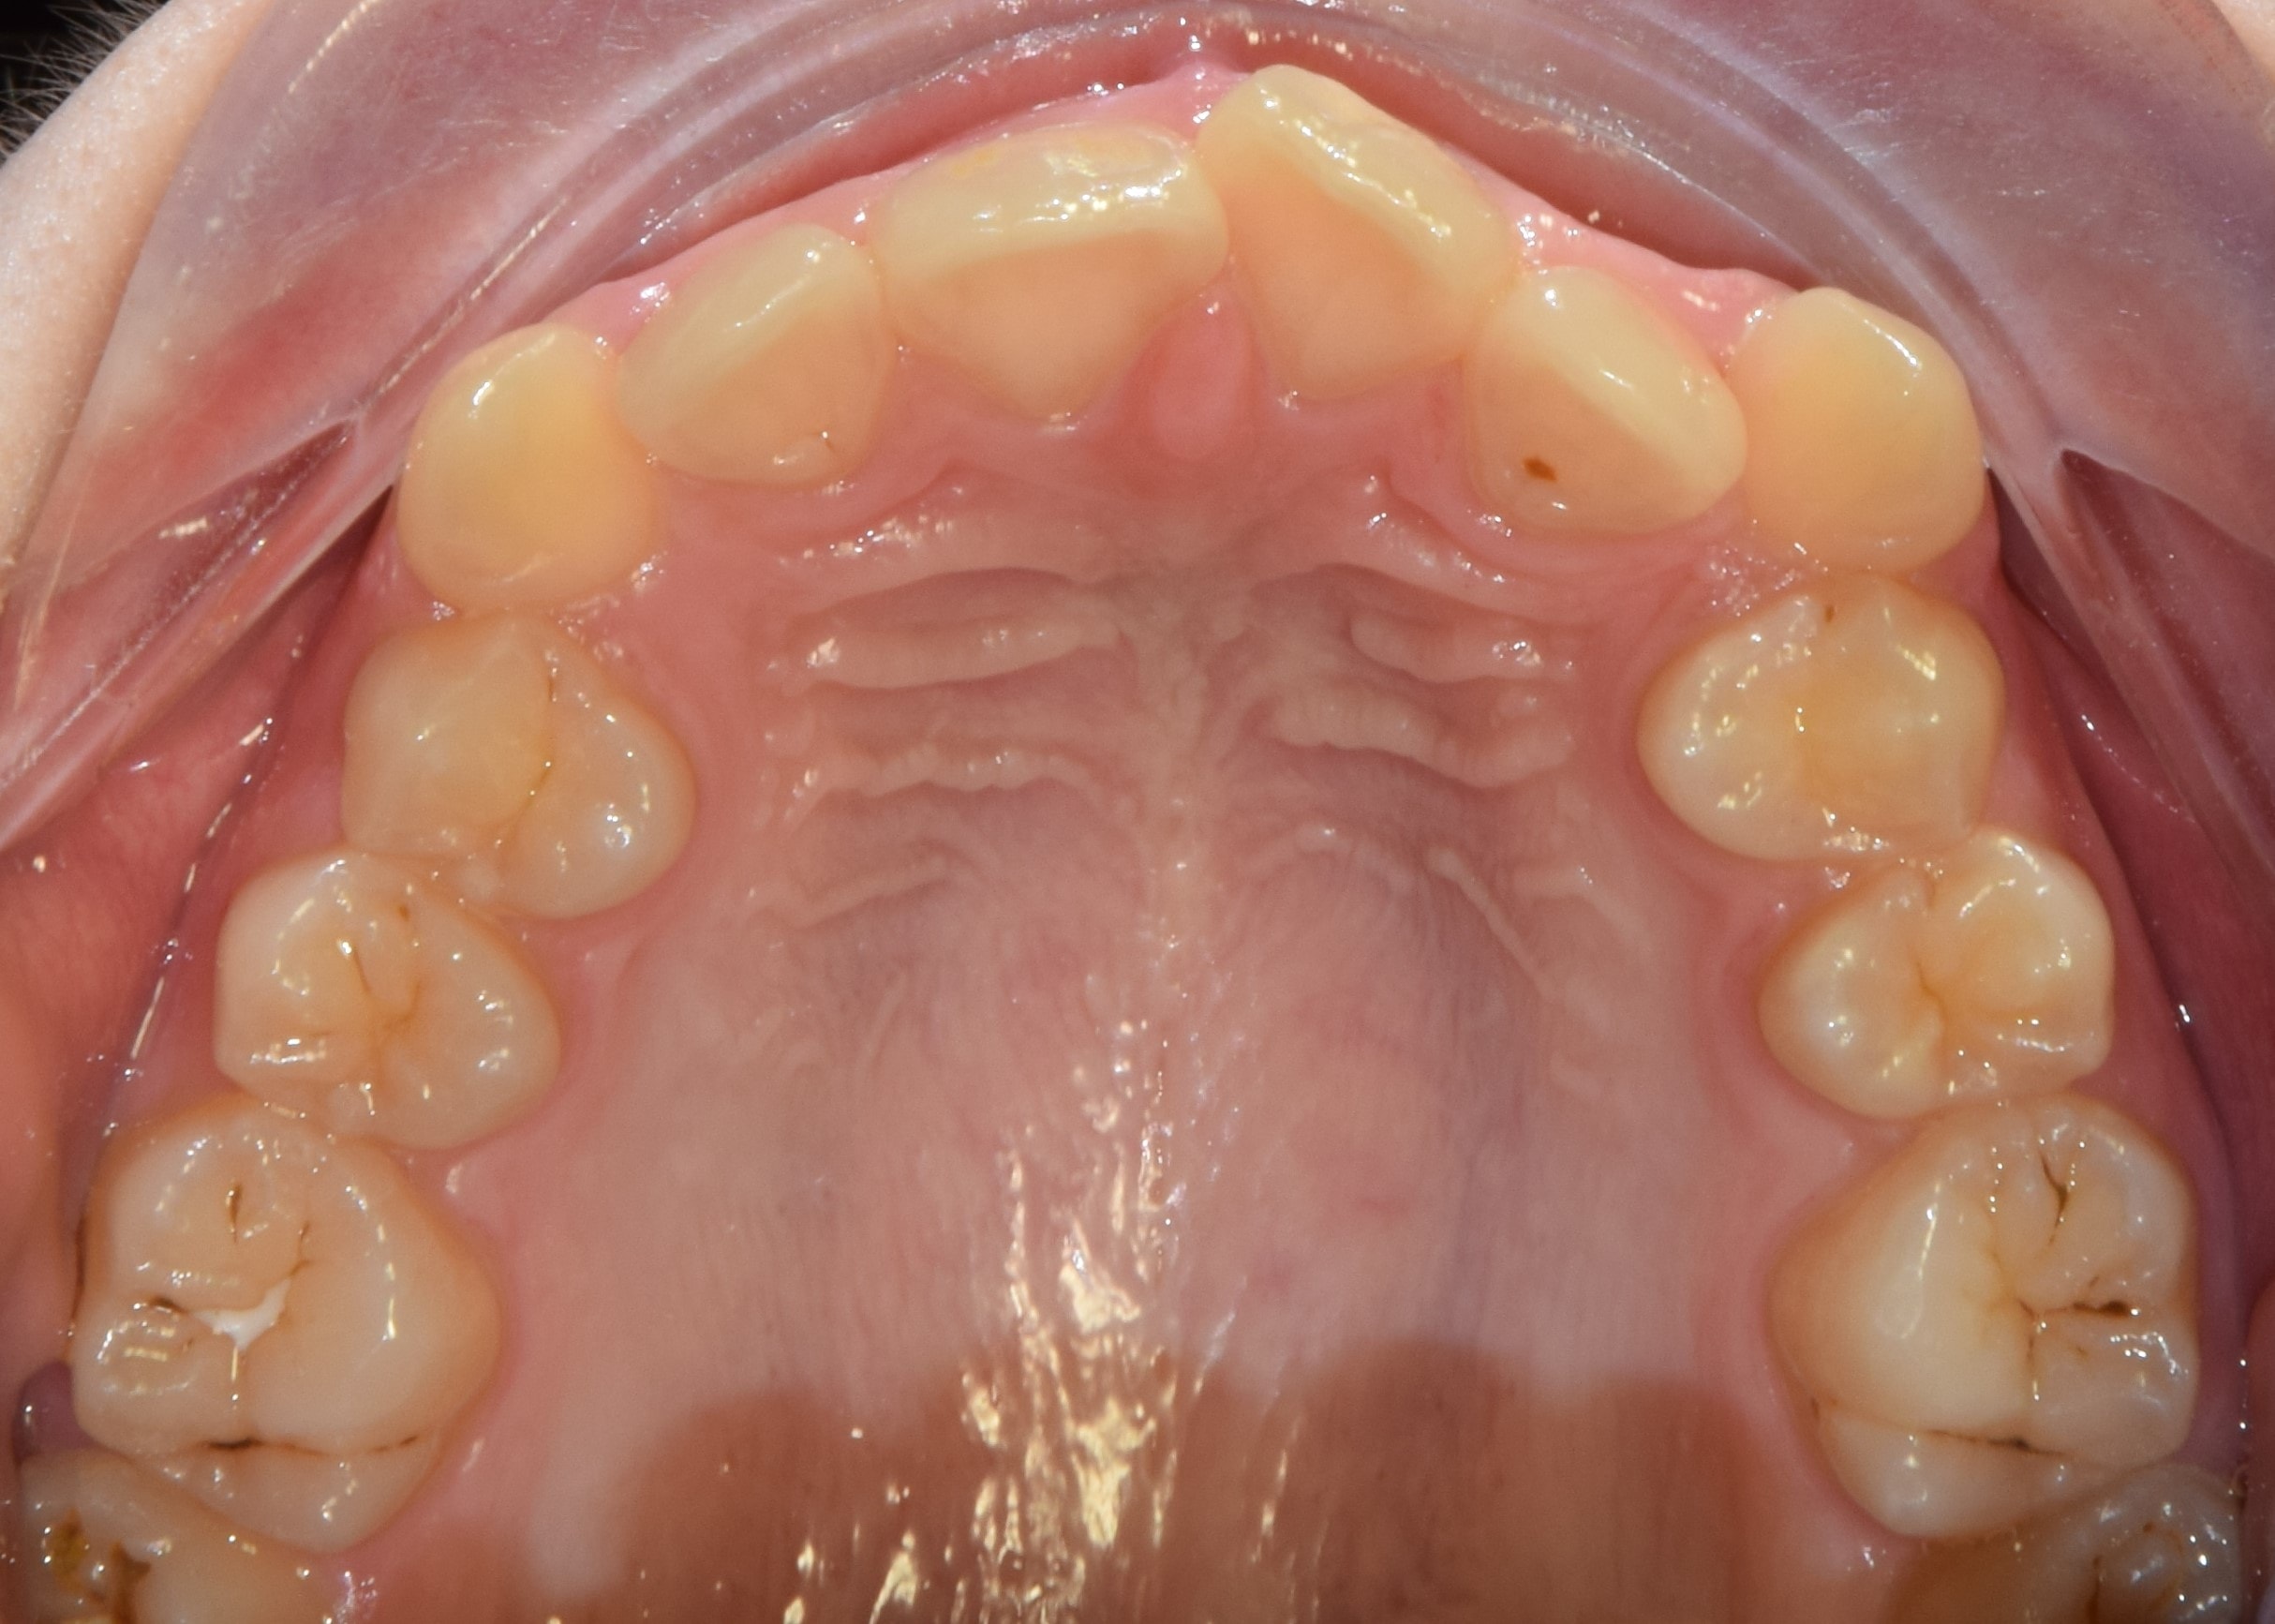

Dezorientációs sín

Általában az alsó fogív fogaira készült átlátszó sínről beszélünk, melynek rágófelszínén átlátszó akrilát van. Súlyosabb állkapocsízületi problémák kezelésénél használjuk. A sín lényege, hogy egyenletes, sima felszínt biztosít a felső fogívvel történő érintkezés során. Ezáltal kiiktatjuk a kóros fogérintkezéseket, relaxáljuk a rágóizmokat, és az ízület a számára legkényelmesebb helyzetbe kerülhet.